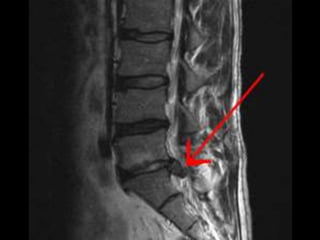

INVESTIGATIONS

MRI

• Clearly superior in the detection of disc

degeneration.

• Allow evaluation of complete spinal group

• Shows:

• Intervertebral disc protrusion.

• Compression of nerve root